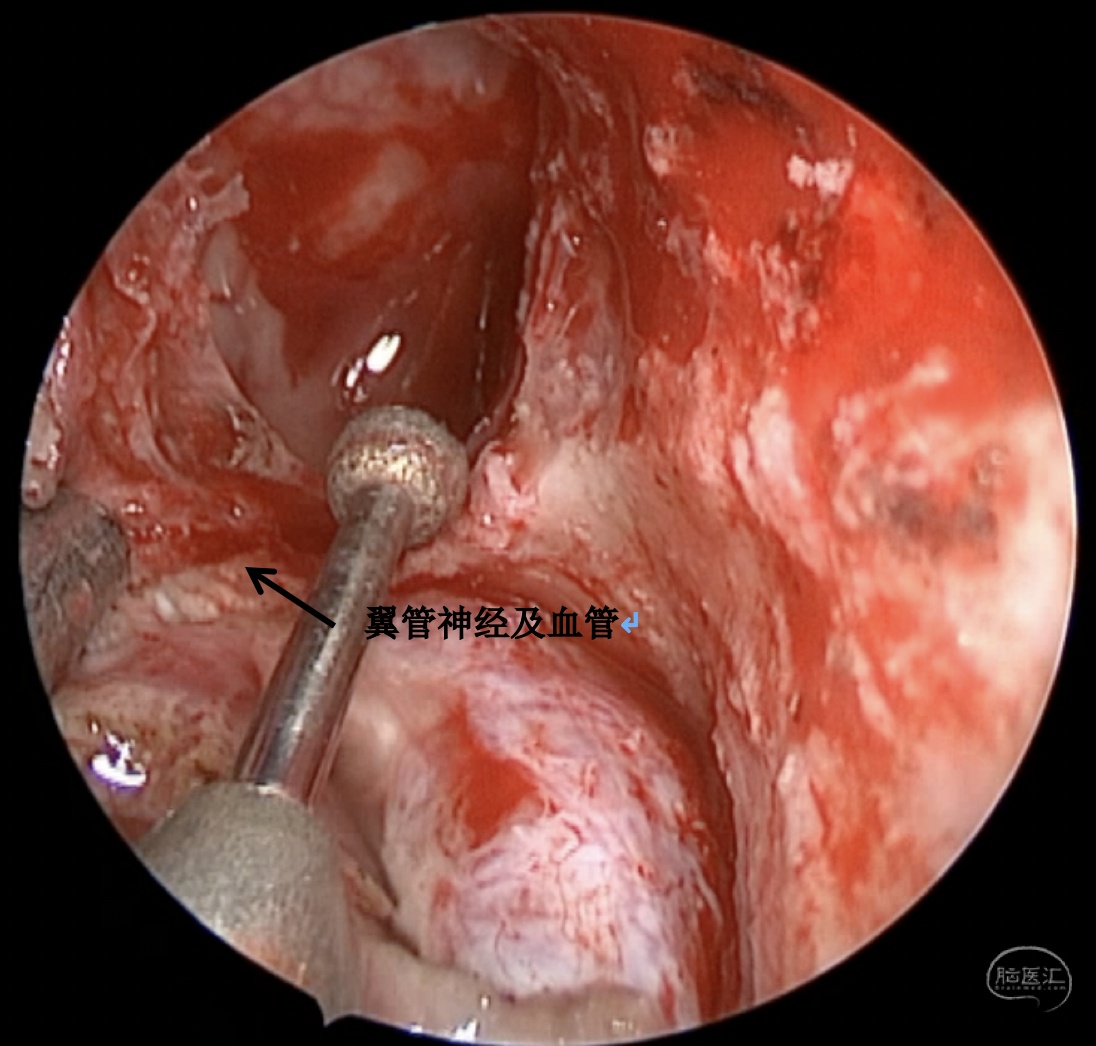

手术方案:内镜经鼻经翼突入路

术中情况:

蝶窦可向翼突根方向过度气化,位于翼管-圆孔连线之外的蝶窦腔隙,称作蝶窦外侧隐窝,是自发性脑脊液漏和脑膜脑膨出的高发区域。蝶窦外侧隐窝脑膜脑膨出伴脑脊液漏在临床上相对少见,这种脑膜脑膨出,如果在出生时出现往往较大,是因为在胚胎形成过程中,神经管未闭所导致。然而,较小的脑膜脑膨出可以多年都不被发现,或者由于外伤、医源性损伤、颅底侵蚀(炎症或者肿瘤)而发生。此外,由于各种原因的颅内压增高,迫使脑组织通过蝶骨的先天性薄弱区疝出,也可以导致该这种疾病发生,本例患者应属于这种情况。

蝶骨在胚胎期由5块软骨板融合形成,如果融合不完全,就会导致先天性骨质缺损。最常见的缺损位于蝶骨大翼,形成一个恒定的外侧颅咽管,也称为Sternberg管,它由Sternberg医师于1888年首先描述。